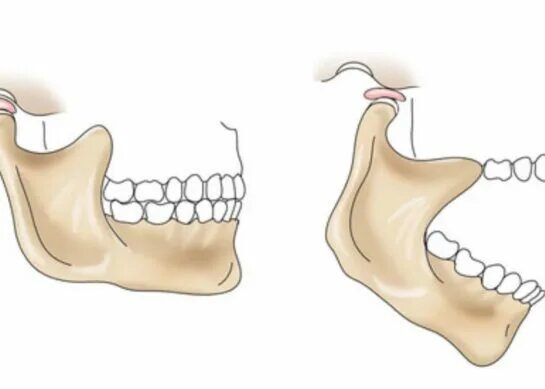

Что делать если заклинило челюсть